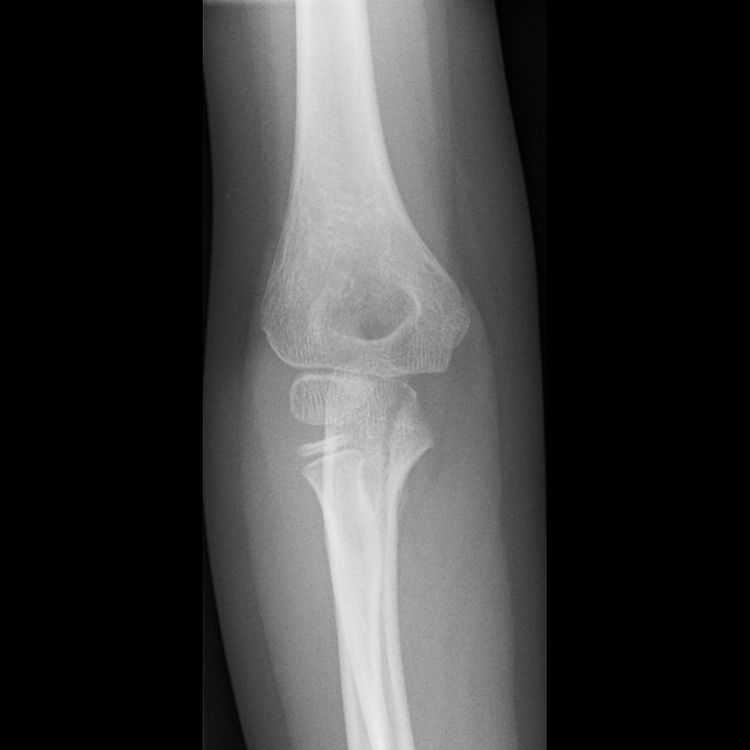

IntraArticular Fracture - हाडासोबतच सांध्याचा पृष्ठभाग सुद्धा फ्रॅक्चर होणे.